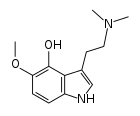

Substituted tryptamines, or serotonin analogues, are organic compounds which may be thought of as being derived from tryptamine itself. The molecular structures of all tryptamines contain an indole ring, joined to an amino (NH2) group via an ethyl (−CH2–CH2−) sidechain. In substituted tryptamines, the indole ring, sidechain, and/or amino group are modified by substituting another group for one of the hydrogen (H) atoms.

| 4-HO-5-MeO-DMT | artificial | 4-OH, 5-OCH3 | CH3 | CH3 | 4-Hydroxy-5-methoxy-N,N-dimethyltryptamine | 2433-31-0 |